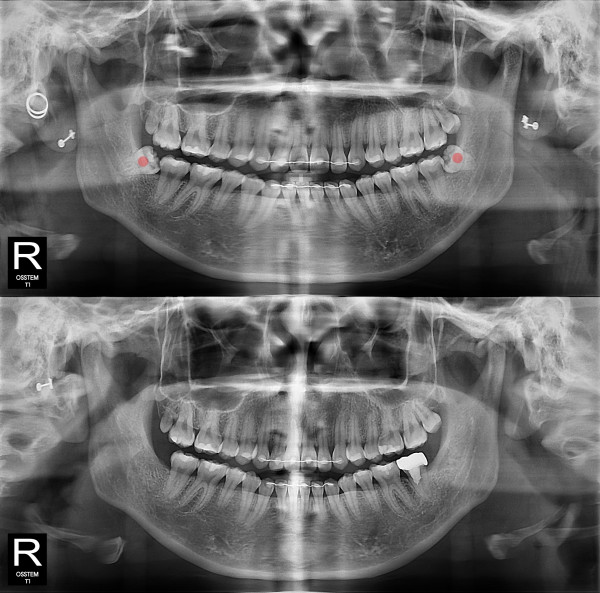

사랑니발치 충치가 심한 사랑니

826e40416d712e6cd444a78bde93df4b_1767857648_0824.jpg